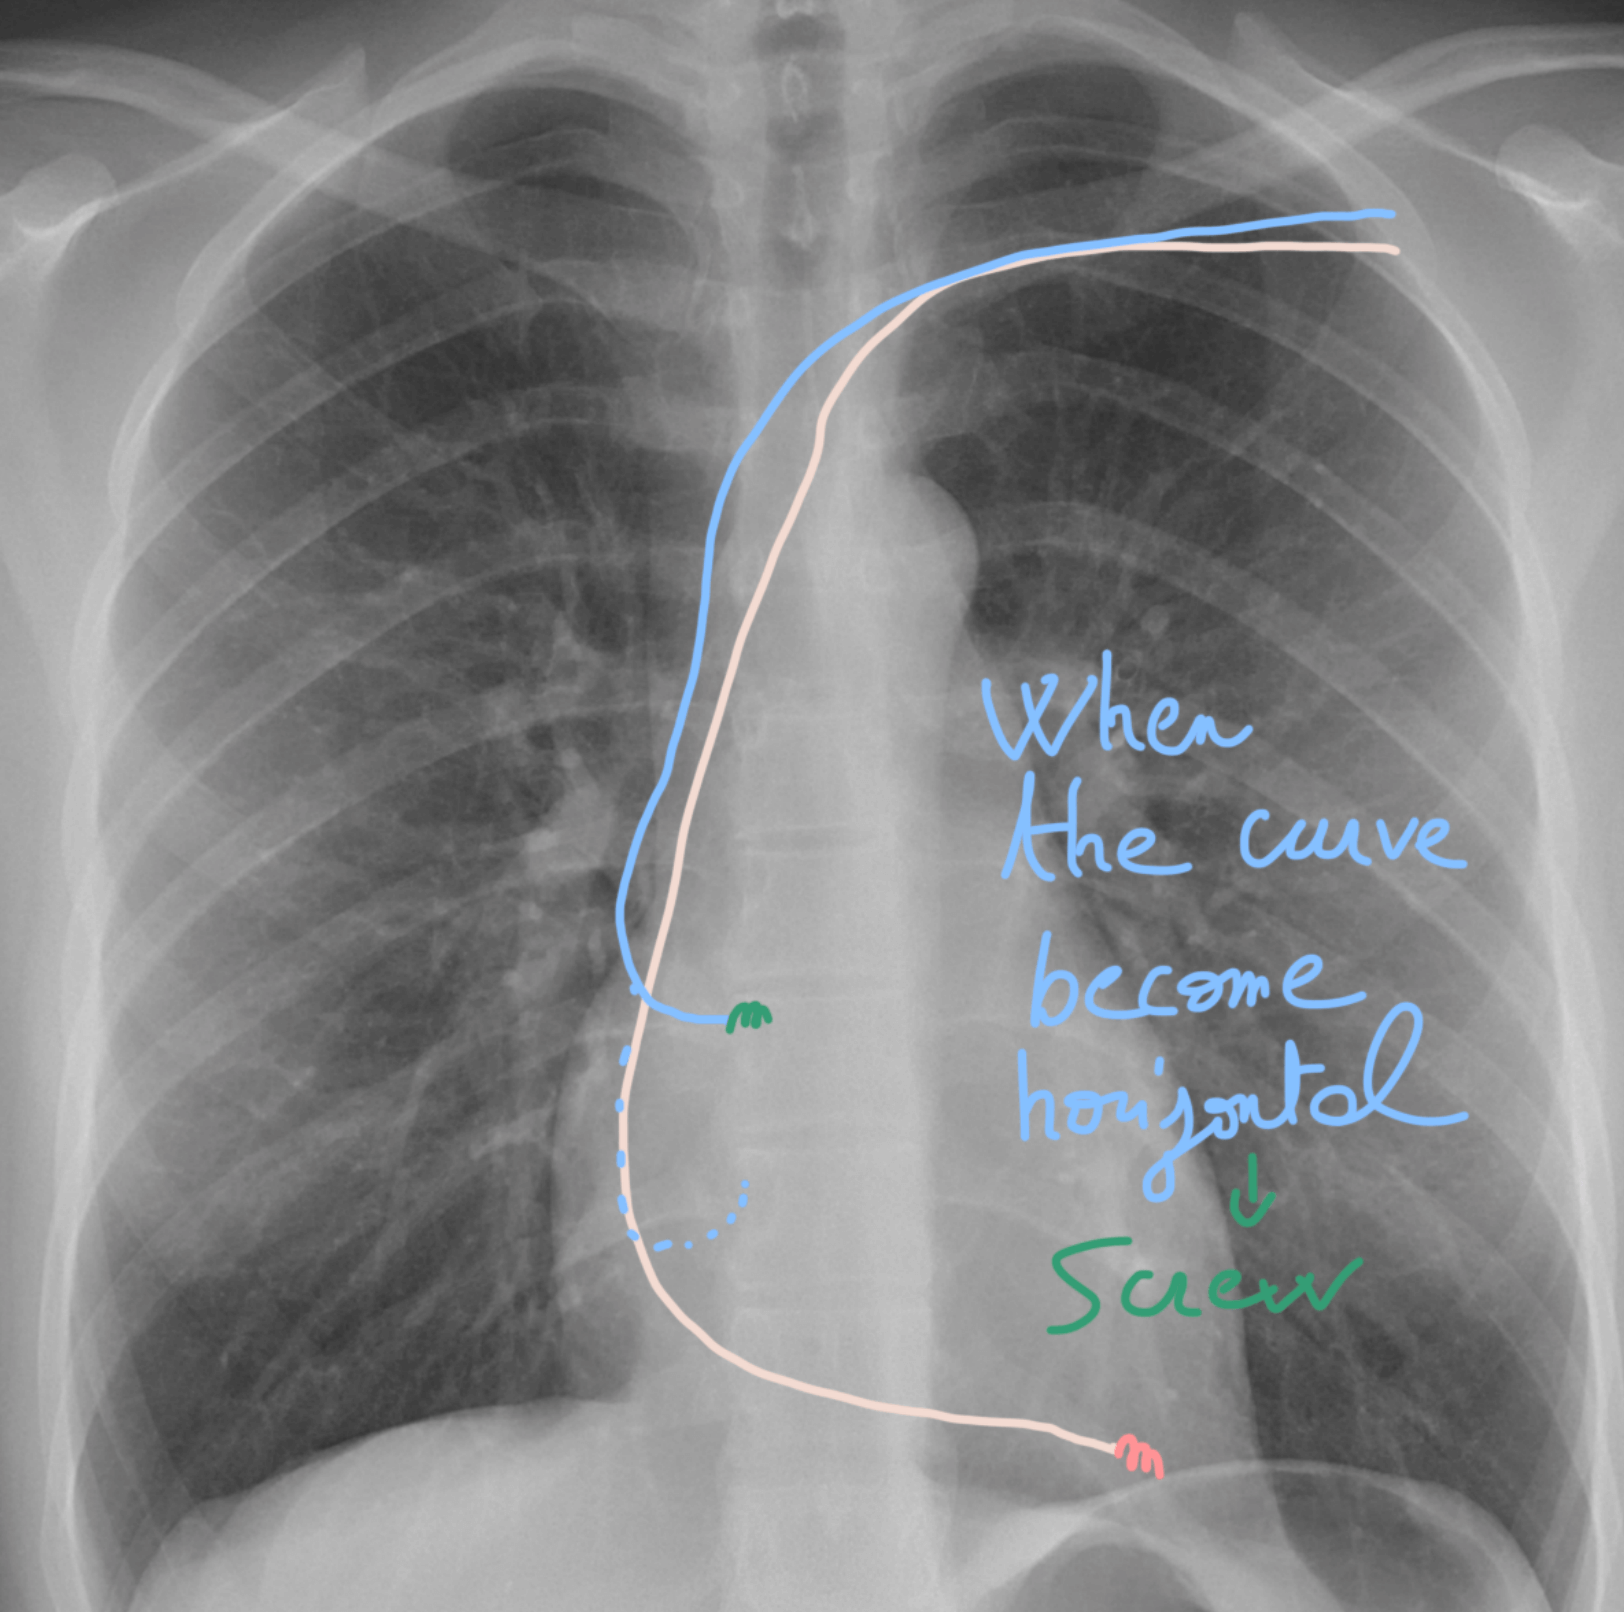

๐ŸŒ€ Step 22: Catch & screw the atrial lead! ๐ŸŽฏ

This part gets a bit more technical โ€” so hang on! ๐Ÿ’ช

๐Ÿ‘‰ Gently pull on the atrial lead until you โ€œcatchโ€ the RAA ๐ŸŽฃ.

Youโ€™ll notice the lead will start to horizontalize ๐Ÿ“ โ€” thatโ€™s your signal!

โœ… As soon as itโ€™s horizontal, itโ€™s time to screw it in ๐Ÿ”ฉ to secure the position.

Think of it like docking a spaceship ๐Ÿ›ธ: once it lines up perfectly, lock it down! ๐Ÿš€